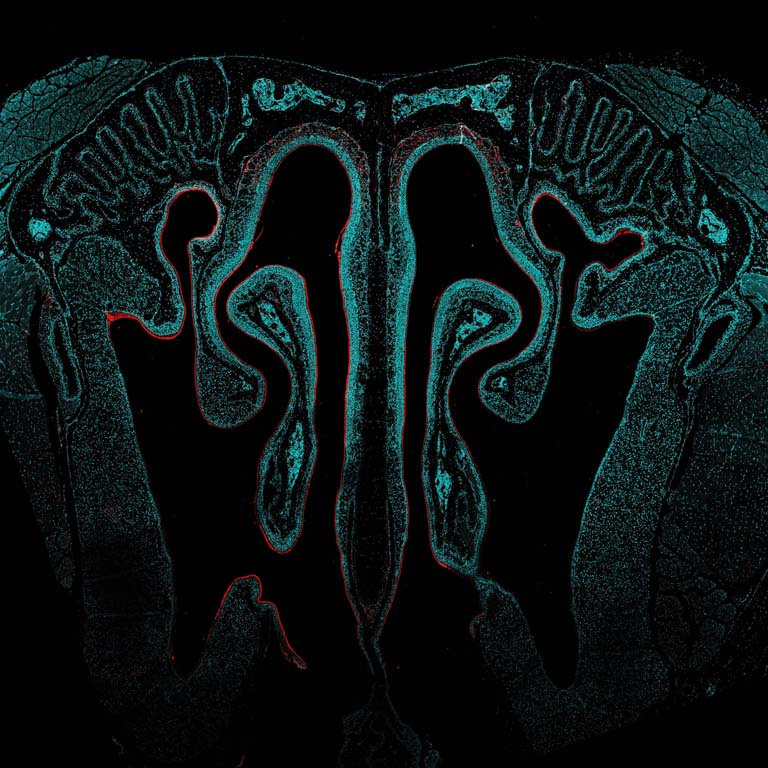

This image shows a cross-section of the nasal passage from a mouse that received an intranasal vaccine developed in the Irvine Lab. The vaccine was designed to be better at transporting into and across the mucosal tissues in the nose, in order to be taken up into the underlying nasal-associated immune tissues in greater amounts to activate a stronger immune response. Compared to injected vaccines, mucosal vaccines (like those administered intranasally) are better at activating a mucosal immune response, which is important for establishing a ‘frontline defense’ of immune protection at mucosal tissues where many infectious diseases are transmitted, such as HIV and SARS-CoV-2. However, mucosal vaccines have historically been plagued by delivery challenges and poor uptake leading to weak immune protection. In this case, our vaccine was engineered to overcome mucosal barriers and evade rapid clearance mechanisms by ‘hitchhiking’ on a chaperone protein found naturally in the mucosal environment. Here, we show that our vaccine is indeed accomplishing this: rather than being rapidly cleared (which is what we observe with a control non-engineered version of this vaccine), our engineered vaccine is sticking around in the nasal cavity for multiple days after administration, lining the nasal tissue and being taken up into the underlying cells.

The vaccine was labeled with a fluorescent molecule so it could be visualized by microscopy. In these images, the signal of the vaccine (in red) can be seen lining the textured nasal tissue (cyan) against the intricate architecture of the nasal cavity (background and negative space).